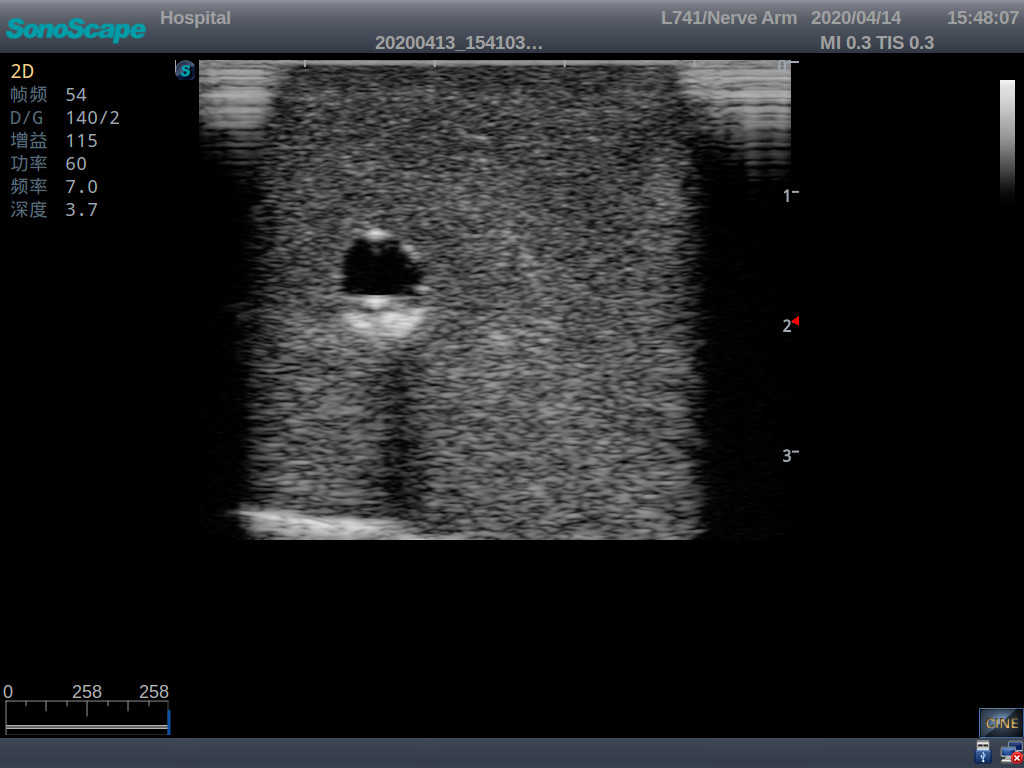

2)   It can be used by real ultrasound machines

3)   Clear and real images of the tissues and organs (basilic vein and superior vena cava)

5)   Observe the guide wire marches

6)   Detect whether the catheter is properly placed